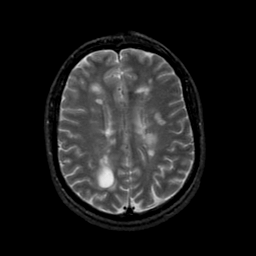

MR Study #21, November 3, 1991 -- Slice #33